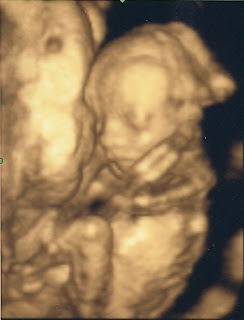

GIRL!!!

I think she looks so cute and feminine in this picture.

Here she is all curled up with her knees right up by her nose.